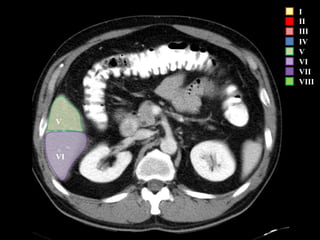

COUINAUD asignó un sistema de numeración para definir la segmentación

hepática.

VI

V

IVb

I

II

III

IV

VII

VIII

I – Entre cava y porta

II – el más superior de los izquierdos

III – Por debajo del II

IV – por delante de la vesícula

V – por detrás de la vesícula

VI – relación con riñón derecho

VII – el más posterior de los segmentos superiores

VIII – domo hepático

Las claves de la segm. Hepática